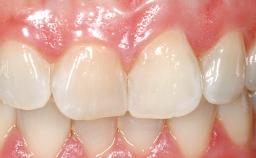

A 33-year-old female patient presented with an upper left central incisor that required extraction after a failed endodontic therapy. The tooth had been traumatized when the patient was a teenager and had undergone several endodontic treatments, including two apicectomy procedures. The patient was in good health and did not smoke. Clinical examination showed that the patient had a high lip line. In full smile, the gingival margins of the upper teeth were visible to the first molars. The gingival margins of central incisors 11 and 21 were only just showing. Examination of tooth 21 confirmed that the tooth was mobile and had hypererupted by 1 mm.

Lip Line No exposure of papillae Exposure of papillae Full exposure of mucosa margin

Periodontal Phenotype Low-scalloped, thick Medium-scalloped, medium-thick High-scalloped, thin

Shape of Tooth Crowns Rectangular Triangular

Soft Tissue Anatomy Intact Defective